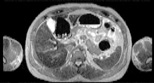

Visible Human male: Sectio transversalis 1546

CT

NMR

Pd                          / T2 \                         T1